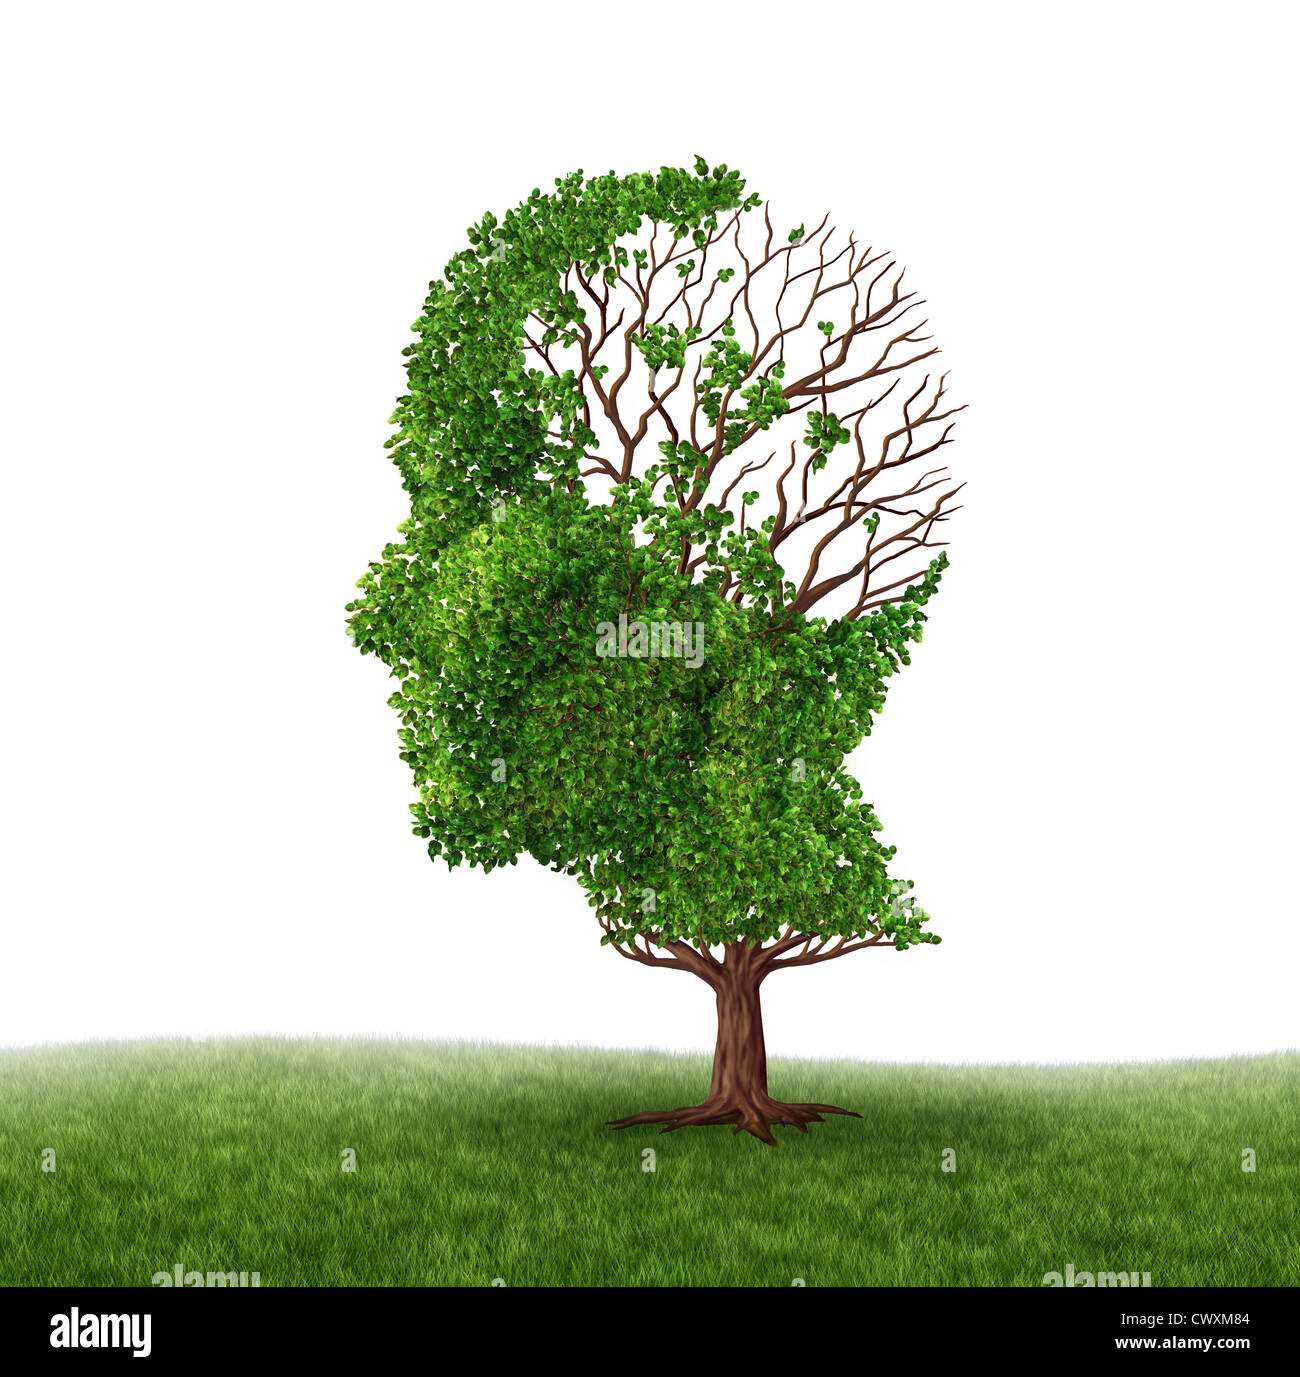

Dementia Brain Tree High Resolution Stock Photography and Images – Alamy

Dementia illness and disease as a loss of brain function and memories …

Dementia Brain Problems stock illustration. Illustration of branches …